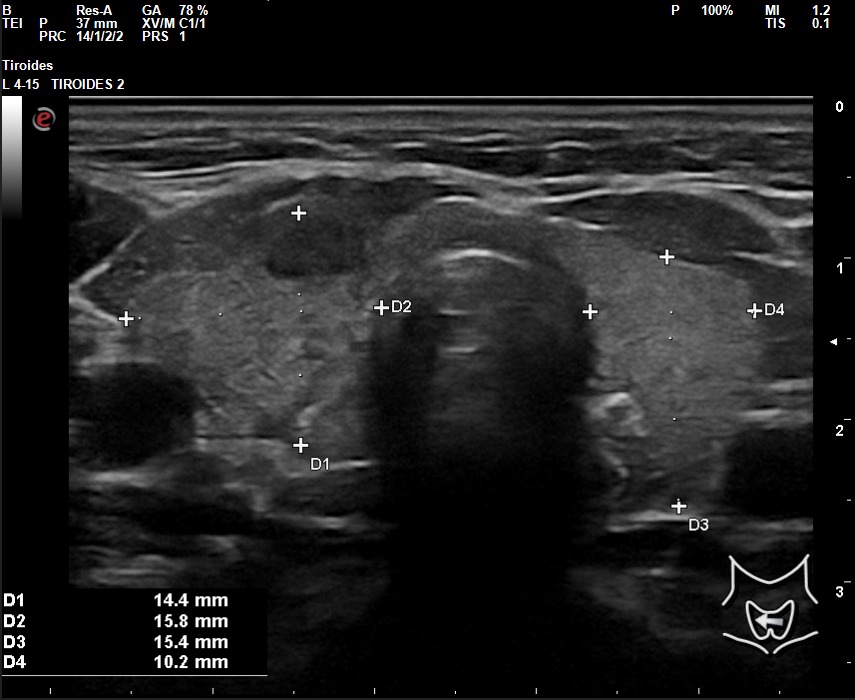

A la exploración ecográfica se observa en lóbulo tiroideo derecho áreas irregulares hipoecoicas sensibles a la sonopalpación con el transductor, con un ligero incremento de la actividad Doppler, asociado a la presencia de adenopatías de características reactivas y/o inflamatorias.

Los hallazgos ecográficos en otro contexto clínico, sin el dolor a la sonopalpación y sin el antecedente de posible viriasis previa, podrían ser muy parecidos al de un nódulo tiroideo sospechoso de malignidad: hipoecoico, márgenes irregulares, etc.